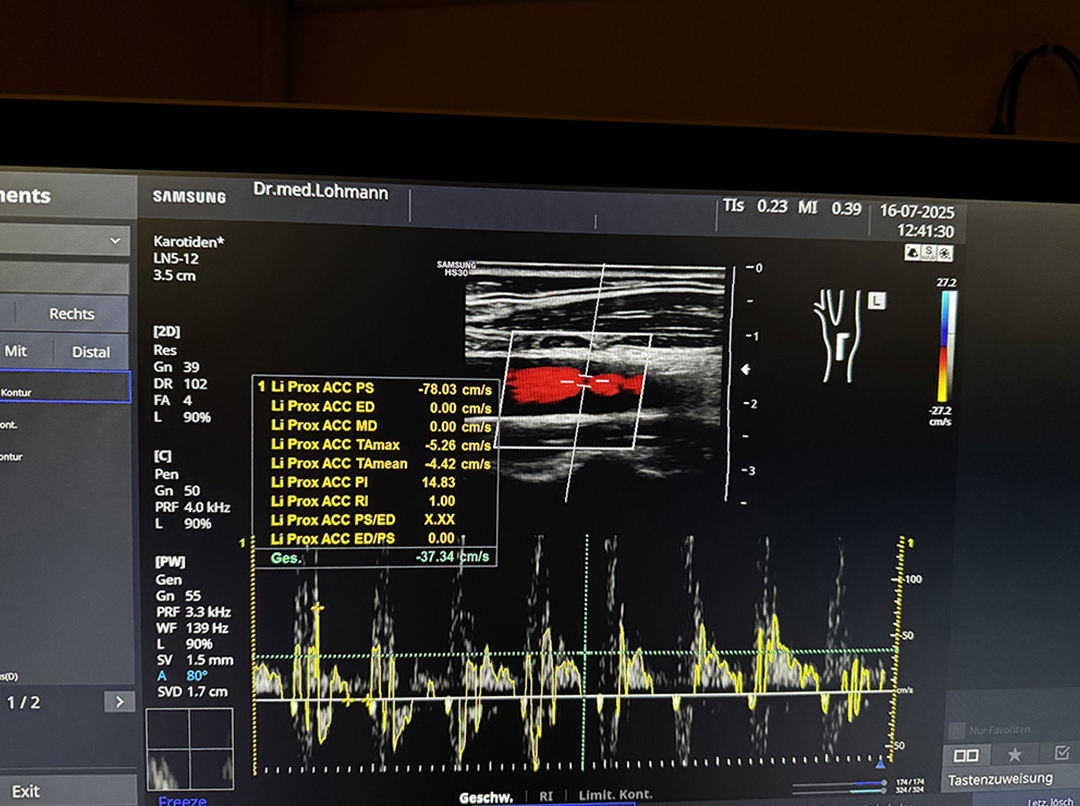

🩻 Farbultraschall

Präzise Diagnostik ohne Strahlenbelastung

Anwendungsgebiete

Unsere Praxis in Saarbrücken bietet ein umfassendes Spektrum der Hals-Nasen-Ohren-Heilkunde – für die Diagnose, Prävention und Therapie akuter wie chronischer Beschwerden. Beschwerden im Hals, Rachen, Kehlkopf, Nase, Nebenhöhlen, Ohren Funktionelle Einschränkungen (z. B. Atmung, Hören, Riechen, Schlucken, Stimme) Vorsorge und Nachsorge bei chronischen Erkrankungen Schlafmedizin Modernste Geräte für Hördiagnostik, Farbdoppler-Ultraschall, schlafmedizinische Untersuchungen und Allergietests ermöglichen eine sichere, zielgerichtete Diagnostik. Wir arbeiten leitlinienbasiert, evidenzgestützt und stets auf dem aktuellen Stand der medizinischen Forschung – mit Fokus auf Ihre individuellen Bedürfnisse und Wünsche. Der Hals ist ein sensibles Zusammenspiel aus Atemwegen, Kehlkopf, Muskulatur und Schleimhäuten. Erkrankungen in diesem Bereich wirken sich oft spürbar auf Stimme, Sprache oder Schluckfunktion aus – mit Folgen für Alltag, Beruf oder Lebensqualität. Heiserkeit, Stimmversagen, Überlastung der Stimme Schluckstörungen (Dysphagie), Globusgefühl im Hals Kehlkopfentzündungen, Reflux-bedingte Beschwerden Beratung bei stimmintensiven Berufen Wir bieten Ihnen in unserer HNO-Praxis in Saarbrücken eine gezielte Abklärung bei akuten oder chronischen Beschwerden im Halsbereich. Ob Heiserkeit, Schluckbeschwerden oder Stimmveränderungen. Die Nase ist nicht nur für das Atmen und Riechen entscheidend – sie beeinflusst auch Schlaf, Stimme und das allgemeine Wohlbefinden. Einschränkungen wie eine verstopfte Nase, chronische Entzündungen oder Geruchsverlust sollten frühzeitig abgeklärt werden. Chronische oder akute Nasennebenhöhlenentzündungen (Sinusitis) Behinderte Nasenatmung, vergrößerte Nasenmuscheln Geruchs- und Geschmacksstörungen Allergische Reaktionen im Nasen-Rachen-Raum In unserer HNO-Praxis in Saarbrücken bieten wir eine präzise Diagnostik und individuell abgestimmte Therapie bei funktionellen Einschränkungen und entzündlichen Erkrankungen der Nase sowie der Nasennebenhöhlen. Hörprobleme, Ohrgeräusche oder Schwindel beeinträchtigen die Lebensqualität oft massiv – ob plötzlich oder schleichend. In unserer HNO-Praxis in Saarbrücken bieten wir eine umfassende Abklärung des Gehörs für Erwachsene, Kinder und Neugeborene. Hördiagnostik (Tonaudiometrie, Sprachaudiometrie, Impedanzmessung) Otoakustische Emissionen und Hirnstammaudiometrie (BERA) Hörscreening für Neugeborene und Kinder Beratung und Versorgung bei Hörverlust, Tinnitus und Schwindel Dank modernster audiologischer Technik können wir Störungen des Hör- und Gleichgewichtsorgans frühzeitig erkennen und gezielt behandeln. Auch bei der Anpassung und Betreuung von Hörgeräten begleiten wir Sie persönlich und kompetent. Kinder benötigen eine besonders einfühlsame medizinische Betreuung – gerade im sensiblen Bereich von Hals, Nase und Ohren. In unserer HNO-Praxis in Saarbrücken stehen daher kindgerechte Diagnostik, Geduld und eine ruhige Atmosphäre im Mittelpunkt. Neugeborenen-Hörscreening & frühkindliche Hördiagnostik Behandlung von Mittelohrentzündungen, Polypen, vergrößerten Mandeln Ambulante Operationen (z. B. Rachenmandelentfernung, Paukendrainage) Beratung bei Sprachentwicklungsverzögerungen und Atemproblemen Wir behandeln akute und chronische HNO-Erkrankungen im Kindesalter – von Hörstörungen über häufige Infekte bis zu Sprachentwicklungsverzögerungen. Ambulante Eingriffe wie die Entfernung von Rachenmandeln oder das Einsetzen von Paukenröhrchen führen wir in enger Kooperation mit einem erfahrenen OP-Zentrum durch. Eltern erhalten bei uns eine individuelle, altersgerechte Beratung. Allergien wie Hausstaub- und Tierhaarallergien sind weit verbreitet und können Alltag, Schlaf und Wohlbefinden stark beeinträchtigen. In unserer HNO-Praxis in Saarbrücken bieten wir gezielte Diagnostik und individuelle Therapien, die über reine Symptombehandlung hinausgehen. Spezifische Immuntherapie (Hyposensibilisierung bei Erwachsenen & Kindern) Pricktest und IgE-Laboranalyse Ergänzende Behandlung mit Naturheilkunde oder Akupunktur Nach ausführlicher Anamnese führen wir gezielte Hauttests (Pricktest) und Laboranalysen durch. Auf Basis der Ergebnisse entwickeln wir einen individuell abgestimmten Behandlungsplan – z. B. in Form einer Hyposensibilisierung (SCIT oder SLIT), gegebenenfalls ergänzt durch Naturheilkundliche Verfahren oder Akupunktur. Der Farbultraschall (Duplexsonographie) ist ein modernes, bildgebendes Verfahren zur Beurteilung von Weichteilen, Lymphknoten und Blutgefäßen – schmerzfrei, schnell und ohne Strahlenbelastung. In unserer HNO-Praxis in Saarbrücken setzen wir diese Technik gezielt zur Diagnostik im Kopf-Hals-Bereich ein. Abklärung von Lymphknoten, Speicheldrüsen, Schilddrüse Untersuchung der Halsgefäße bei Schwindel, Ohrgeräuschen, Kopfschmerzen Verlaufskontrolle nach Operationen oder bei chronischen Erkrankungen Gerade bei unklaren Schwellungen, Schilddrüsenveränderungen oder Durchblutungsstörungen liefert der Farbultraschall wertvolle Informationen – auch bei Schwindel, Tinnitus, Kopfschmerzen oder nach Operationen erweitert er das diagnostische Spektrum, ohne den Körper zu belasten. Als nichtinvasive Methode ist er sowohl für Erwachsene als auch für Kinder hervorragend geeignet und ergänzt unsere HNO-Diagnostik ideal. Einige HNO-Erkrankungen lassen sich durch gezielte, ambulante Eingriffe effektiv und dauerhaft behandeln. In unserer Praxis in Saarbrücken bieten wir Ihnen umfassende operative Betreuung – von der Diagnostik über den Eingriff bis zur Nachsorge – alles aus einer Hand. Einlage von Paukendrainagen Entfernung der Rachenmandel (Polypenoperation bei Kindern) Nasenmuschelverkleinerung / Radiofrequenzchirurgie Nasenscheidewandkorrektur und Kieferhöhlenoperationen Gaumensegelstraffung bei Schnarchen (UPPP) In Kooperation mit dem Ambulanten Operationszentrum am Boxberg in Neunkirchen führen wir Eingriffe wie Polypenentfernungen, Paukendrainagen oder Nasenscheidewandkorrekturen. Dabei legen wir besonderen Wert auf individuelle Aufklärung, kurze Wege und eine schnelle Erholung. Ob für bestimmte Berufe oder offizielle Atteste – in unserer HNO-Praxis in Saarbrücken führen wir qualifizierte Tauglichkeitsuntersuchungen durch. Dabei prüfen wir gezielt die relevanten Funktionen von Ohren, Nase und Atemwegen. Berufliche Eignungsuntersuchungen Medizinische Gutachten und Atteste bei HNO-relevanten Beschwerden Die Untersuchung erfolgt individuell und auf die jeweilige Anforderung zugeschnitten. Je nach Einsatzbereich prüfen wir z. B. das Hörvermögen, den Druckausgleich, die Nasenatmung oder den Zustand des Gleichgewichtsorgans. Sie erhalten im Anschluss ein aussagekräftiges ärztliches Attest nach den jeweils gültigen medizinischen Standards. Impfungen sind ein wichtiger Bestandteil der medizinischen Prävention – für Ihre eigene Gesundheit und die Ihrer Mitmenschen. In unserer HNO-Praxis in Saarbrücken beraten wir Sie individuell zu empfohlenen Impfungen und führen diese direkt in der Praxis durch. Grippe-, Pneumokokken- und COVID-19-Impfung Impfung gegen Gürtelrose und HPV Auffrischimpfungen gegen Tetanus, Diphterie, Polio, Keuchhusten, Hepatis A und B, FSME Reiseimpfungen je nach Reiseziel, Infektionsrisiko und Reisedauer Individuelle Impfberatung Ob Standardimpfungen für Erwachsene, Auffrischungen, Reiseimpfungen oder gezielter Schutz z. B. vor Grippe oder Gürtelrose: Wir prüfen Ihren Impfstatus, klären auf und führen auf Wunsch die entsprechenden Impfungen durch. Dabei richten wir uns nach den aktuellen Empfehlungen der STIKO und passen unsere Empfehlungen an Ihre persönliche Lebenssituation an – z. B. bei Vorerkrankungen, Alter oder beruflichen Anforderungen. In bestimmten Fällen benötigen Sie eine fachärztliche Einschätzung oder ein medizinisches Gutachten – sei es für Versicherungen, Behörden, Gerichte oder zur Klärung gesundheitlicher Einschränkungen. Fachärztliche Gutachten bei Hör-, Stimm- oder Gleichgewichtsstörungen Gutachten für Versicherungen, Renten- oder Berufsunfähigkeitsverfahren Dr. Julia Lohmann erstellt auf Basis gründlicher Untersuchung und Diagnostik gutachterliche Stellungnahmen zu HNO-spezifischen Beschwerden. Dabei legen wir großen Wert auf medizinische Sorgfalt, nachvollziehbare Befunde und eine klare Dokumentation, die sowohl medizinischen als auch rechtlichen Anforderungen gerecht wird. Infusionen ermöglichen eine schnelle Versorgung des Körpers mit wichtigen Vitaminen, Mineralstoffen oder entzündungshemmenden Wirkstoffen – direkt über den Blutkreislauf. In unserer Praxis bieten wir verschiedene Infusionstherapien an, abgestimmt auf Ihren individuellen Bedarf. Hochdosierte Vitamin-C-Infusionen B-Vitamin-Infusionen Kortison-Infusionen bei Hörsturz, Tinnitus oder Schwindel Gerne beraten wir Sie hierzu ausführlich. Neben der schulmedizinischen Behandlung setzen wir in unserer HNO-Praxis in Saarbrücken auch auf bewährte naturheilkundliche Verfahren. Unterstützung bei Erschöpfung, hormoneller Dysbalance oder Wundheilung Schmerzlinderung Schlafstörungen, Tinnitus, stressbedingte Beschwerden Allergien, Infektanfälligkeit, chronische Entzündungen Die Therapien werden individuell auf Ihre Beschwerden abgestimmt und lassen sich je nach Krankheitsbild sinnvoll mit klassischen Verfahren kombinieren – für eine ganzheitliche Wirkung. Um eine effektive Behandlung zu ermöglichen, ist es entscheidend, die genauen Ursachen einer Erkrankung zu kennen. In unserer Praxis setzen wir mikrobiologische Untersuchungen ein, um Krankheitserreger präzise zu identifizieren – z. B. bei Infekten im Hals-, Nasen- oder Ohrenbereich. Abklärung bei häufigen oder langanhaltenden Infekten Nachweis von Erregern im Rachen, der Nase oder den Ohren Unterstützung bei der gezielten Auswahl von Antibiotika oder weiteren Therapien Durch gezielte Abstriche, Schnelltests oder Laboranalysen können bakterielle, virale oder auch pilzbedingte Infektionen schnell und zuverlässig erkannt werden. Die Ergebnisse helfen uns dabei, eine exakt auf den Erreger abgestimmte Therapie zu planen – sei es durch den gezielten Einsatz von Antibiotika oder ergänzende Maßnahmen. Früherkennung und strukturierte Nachsorge sind entscheidend für den Behandlungserfolg bei Tumorerkrankungen im HNO-Bereich. In unserer Praxis bieten wir Ihnen zuverlässig Vorsorgeuntersuchungen sowie eine engmaschige Begleitung nach abgeschlossener Therapie. Tumornachsorge bei HNO-Erkrankungen (z. B. Rachen, Kehlkopf, Nase) Vorsorgeuntersuchungen zur frühzeitigen Erkennung von Veränderungen Zusammenarbeit mit onkologischen Zentren und Kliniken Mit modernen Untersuchungsverfahren, langjähriger Erfahrung und viel Sorgfalt kontrollieren wir regelmäßig mögliche Rückfallzeichen, dokumentieren Veränderungen und beraten Sie umfassend zu therapeutischen Optionen. Unsere Nachsorge erfolgt nach aktuellen Leitlinien und immer in enger Abstimmung mit weiteren behandelnden Fachärzt und Kliniken – für Ihre Sicherheit und Ihr Vertrauen. Moderne HNO-Medizin für Erwachsene, Kinder und Familien.